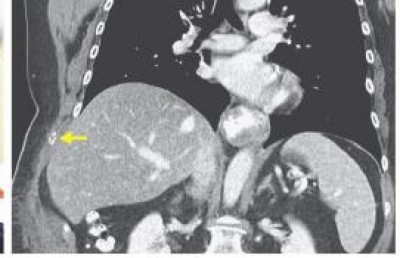

އެމެރިކާގެ މެސަޗޫސެޓްސްގައި ދިރިއުޅޭ މި އަންހެންމީހާގެ ސީޓީ ސްކޭން ހަދަން ޑޮކްޓަރު އެންގީ އޭނާގެ މެޔާއި ބަނޑުގައި ކަޅުވެފައި ހުރި ތަން ފެނިގެންނެވެ. ސީޓީ ސްކޭން އިން ދެއްކި ގޮތުގައި އަންހެންމީހާގެ މޭ ކަށިގަނޑެއް ބިނދި އެއްކޮށް އޮތީ ވަކިވެފަ އެވެ.

އިތުރު ޓެސްޓްތައް ހެދުމުން ޔަގީންވި ގޮތުގައި އަންހެންމީހާގެ ހަށިގަނޑުގައި ހޯއްގޮވާ ކެއްސުން ނުވަތަ ވޫޕިން ކޯފް ޖައްސާ ޖަރާސީމު ހުއްޓެވެ.